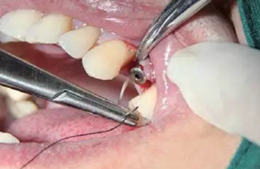

翻瓣與植入種植體

注意翻瓣不能太大,只需將窩洞頂端及周邊充分暴露即可。檢查種植窩洞頂端邊緣的骨壁情況,將窩洞頂端的高點去除,防止其干涉愈合基臺的就位。植入種植體植入時通過扭力扳手來確定最終的植入扭力,并判斷是否合適放置愈合基臺,也可以通過松動度測量儀測量ISQ值來判斷。

圖4 小翻瓣暴露窩洞頂端并去除高點